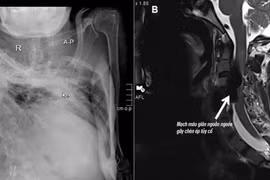

Hiếm gặp: Rò động tĩnh mạch cột sống liệt tứ chi trên nền gù vẹo nặng

Bệnh viện Đa khoa Quốc tế S.I.S Cần Thơ vừa can thiệp mạch hiếm gặp cứu sống người đàn ông gù vẹo cột sống 30 năm, liệt tứ chi do rò động tĩnh mạch cột sống.